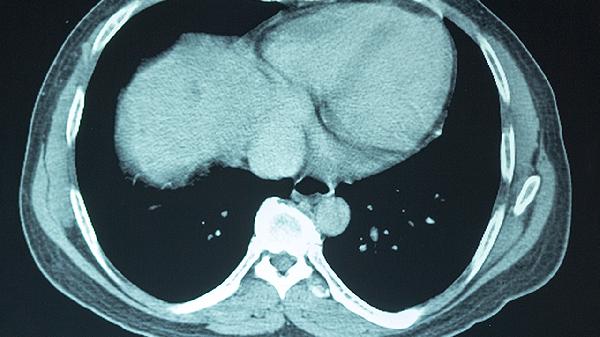

冠心病心肌缺血或心力衰竭时泵血功能下降,可能导致脑灌注不足。常伴有胸闷、下肢水肿等症状。可遵医嘱使用单硝酸异山梨酯缓释片改善心肌供血,或呋塞米片减轻心脏负荷。严重冠脉狭窄需考虑支架植入术。

慢性阻塞性肺疾病或重症肺炎会影响气体交换效率。患者多有咳嗽、咳痰、呼吸困难等表现。急性发作期可使用布地奈德福莫特罗粉吸入剂扩张支气管,合并感染时联用盐酸莫西沙星片抗炎治疗。终末期患者需长期家庭氧疗。